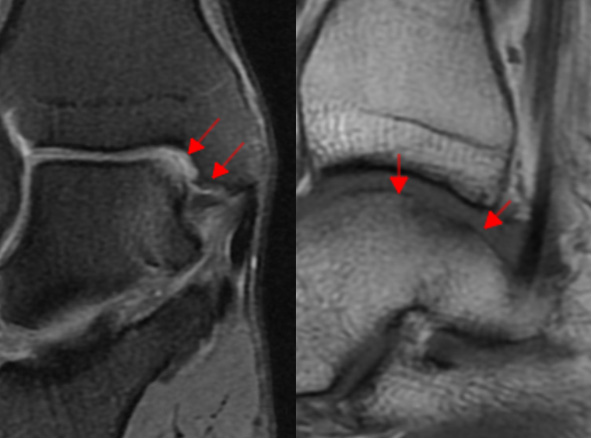

거골의 내측부 연골 병변에 대해서 관절경을 통해 미세천공술과 콜라겐 주입술을 시행하였으며,

수술 5개월째 결손 부위에 연골이 잘 생성되어 있는 소견이 관찰되었습니다.